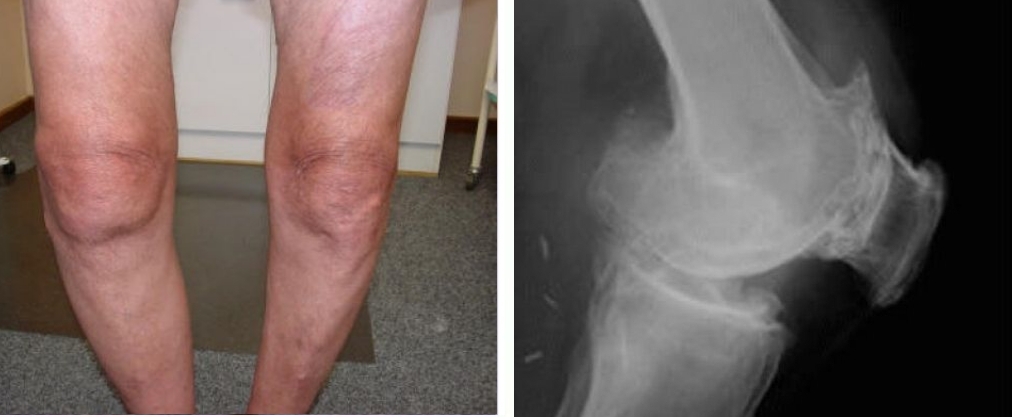

Kerusakan sendi lutut, kelengkungan parah pada lutut, serta nyeri tajam yang terus-menerus, terutama saat melakukan gerakan sekecil apa pun.

Kerusakan dan degradasi tulang rawan lutut, nekrosis jaringan, kehilangan sendi sepenuhnya, dan amputasi.

Wanita, 44 tahun. Kelengkungan lutut yang parah, posisi lutut melengkung ke dalam. Pengobatan dengan "Jointlite" berlangsung 2,5 bulan hingga pemulihan total.